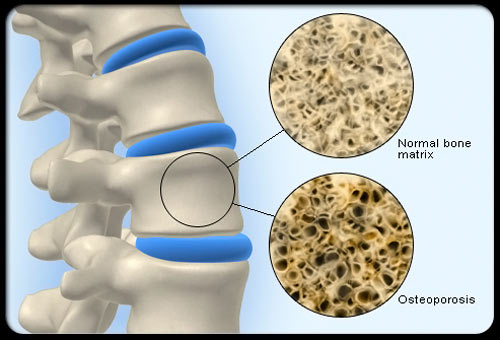

درد دیسک کمر معمولاً در ناحیه تحتانی کمر شروع و به ناحیه ساکروایلیاک و گاهی تا پشت ران تیر می کشد. باید توجه داشت کمردرد تنها در اثر بیماری دیسک کمری نیست . نواحی دیگری از ستون فقرات شامل مفاصل فاست ها ، لیگمان های طولی و پریوست مهره ها می توانند منشأ درد کمری و پشت ران باشند.